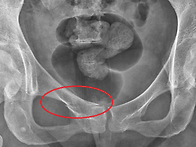

Pubis Fracture의 보존..

센터장 20.10.29Pubis Fracture의 발생 원인. Pubis 부근의 골절은 대게..